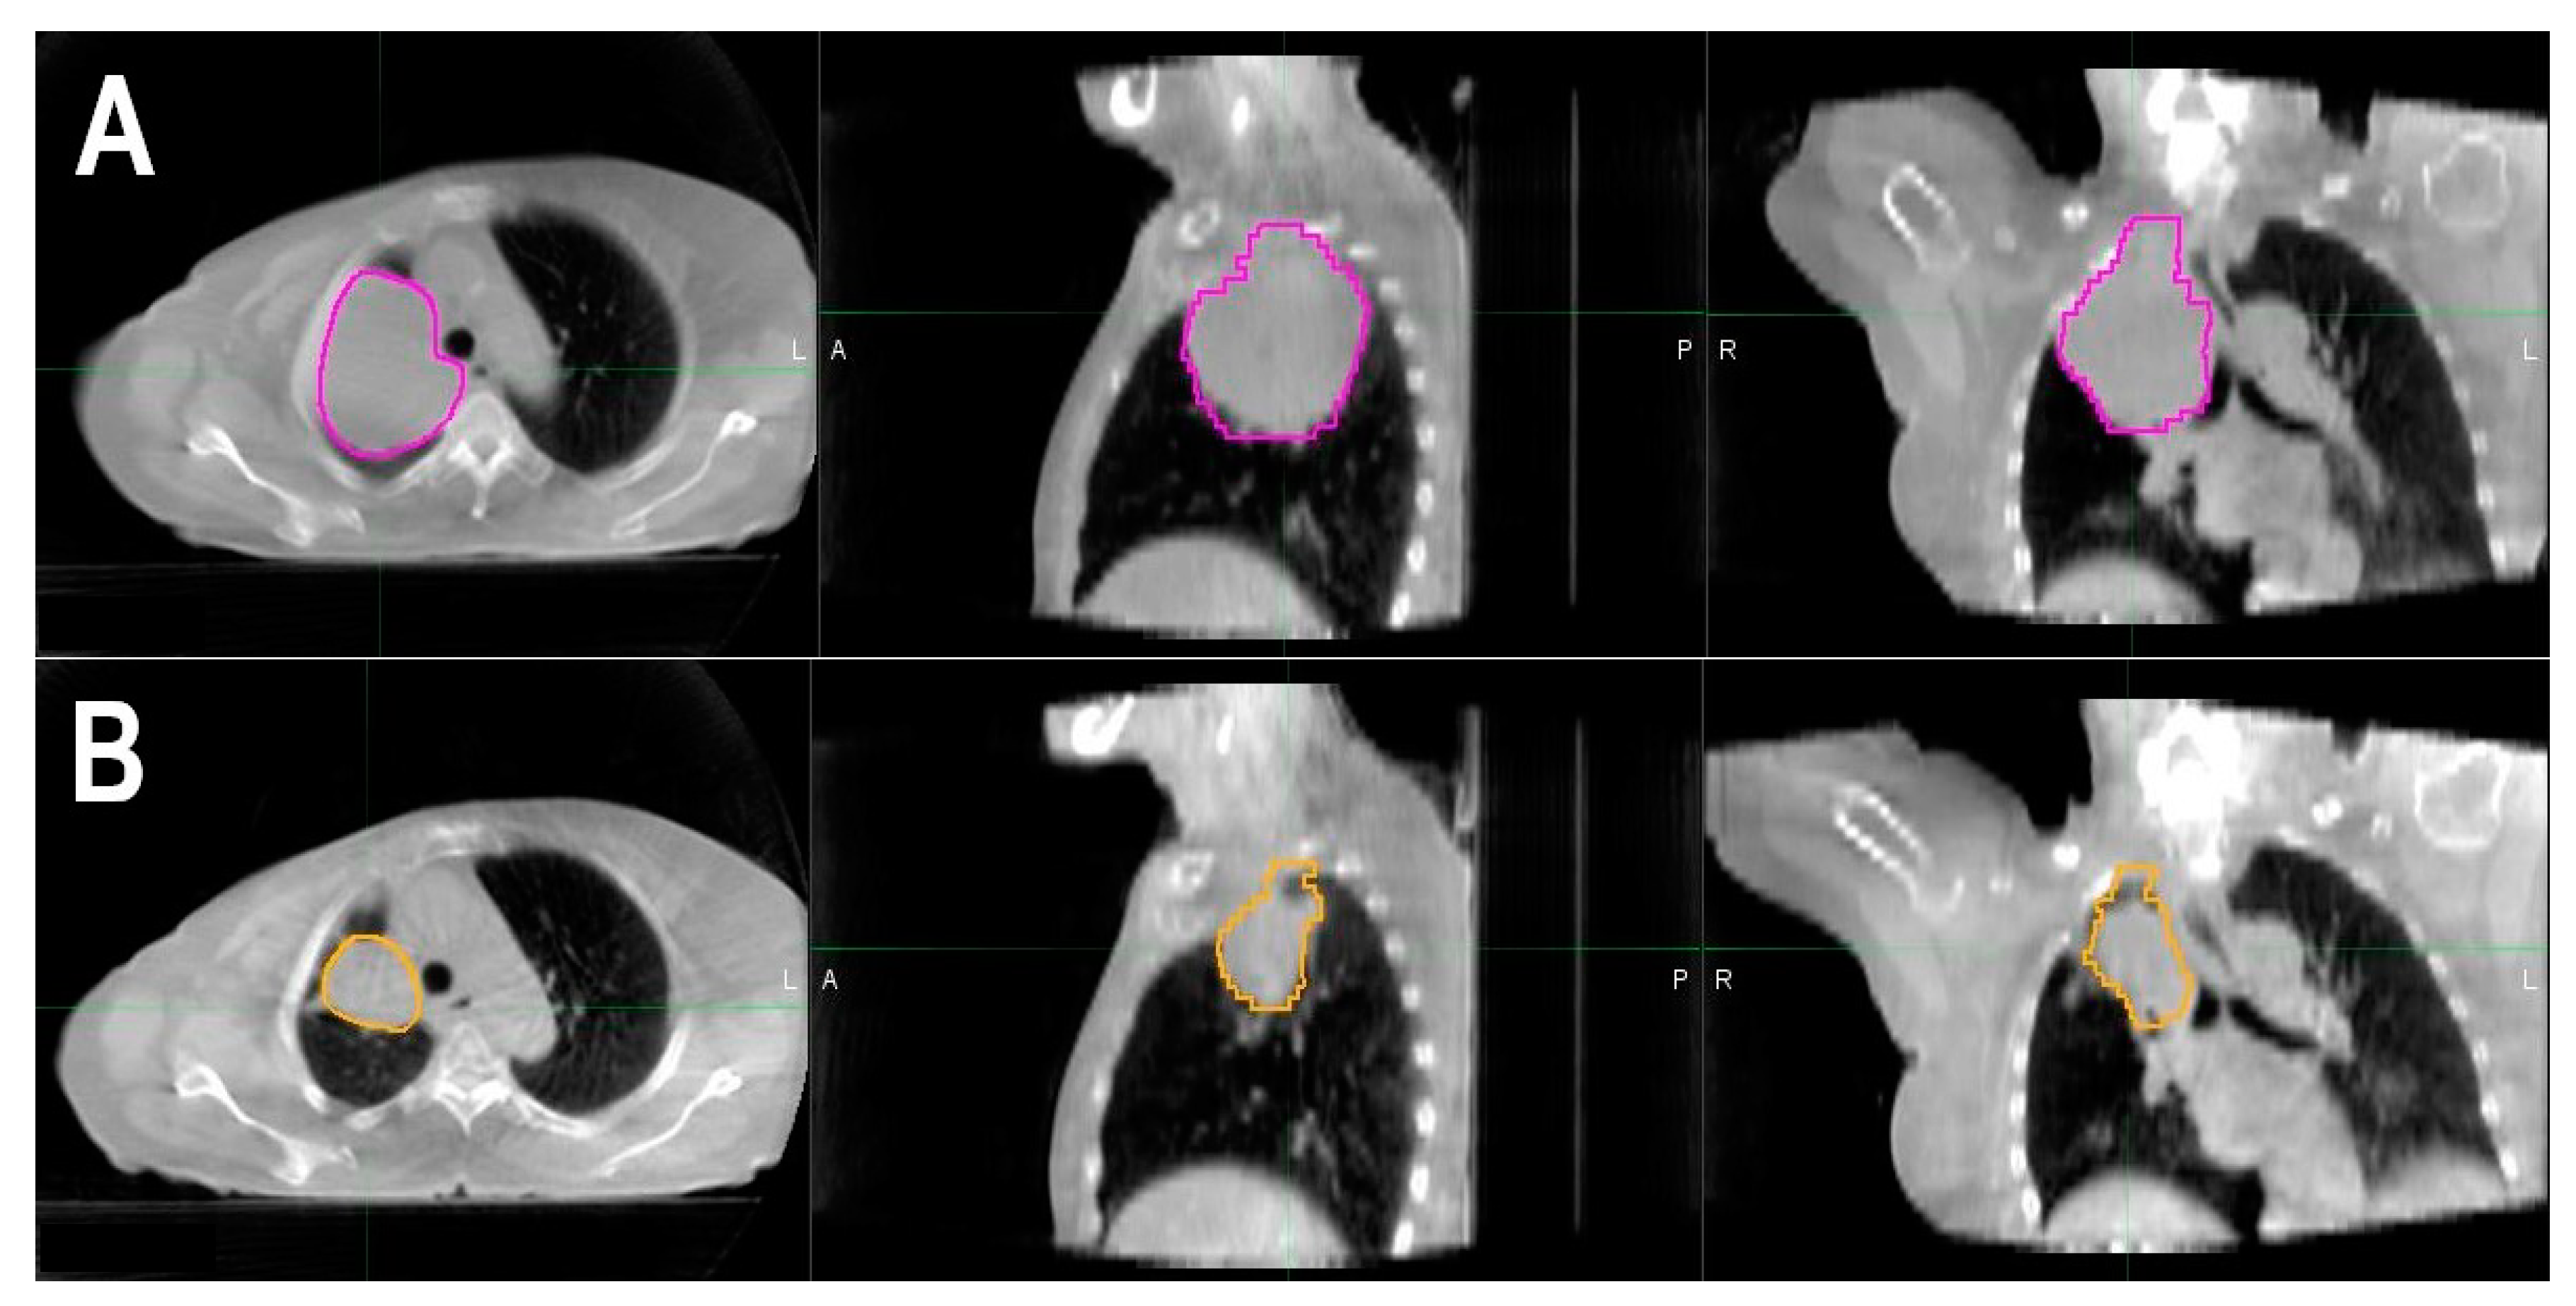

2.2. Tumor Regression

3.2. Volumetric Tumor Response and Survival Analysis